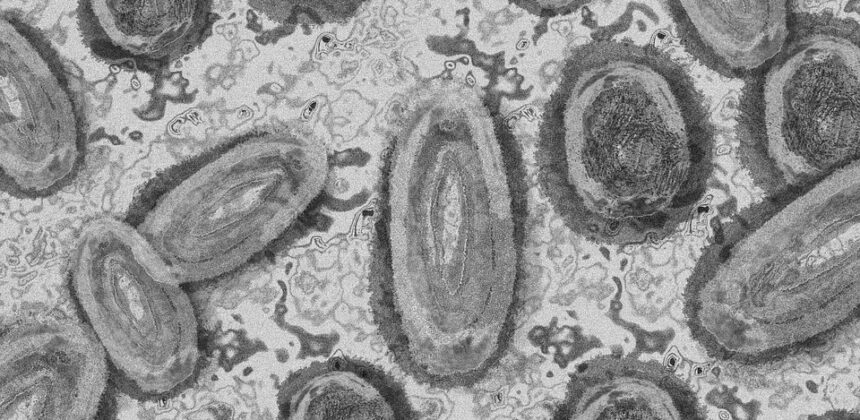

A vacina não foi feita exclusivamente contra a varíola do macaco e sim contra a varíola humana, doença que foi considerada erradicada pela OMS em 1980. Mas, como os dois vírus fazem parte da família ortopoxvírus, o imunizante é usado para prevenir também contra a monkeypox.